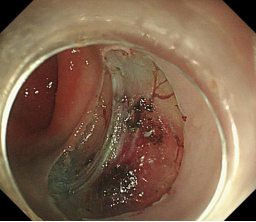

食管胃底静脉曲张内镜下套扎、组织胶治疗

肝硬化食管和胃底静脉曲张破裂出血的内镜下组织胶注射和套扎序惯治疗